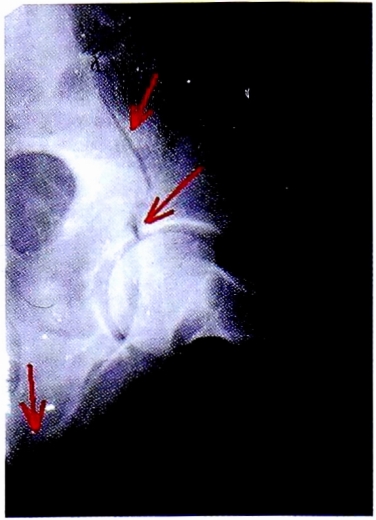

После выполнения прицельной рентгенографии в косой подвздошной проекции по методике НМИЦ TO, выявлена линия перелома, проходящая через крыло подвздошной кости, сурсил и нижние отделы передней колонны. Также на прицельной рентгенограмме отчетливо видна интактность задних отделов вертлужной впадины (рис. 13).

Рис. 13. Рентгенография левого тазобедренного сустава в косой-подвздошной проекции, выполнена по методике НМИЦ ТО. Стрелками показана линия перелома в местах прохождения через визуализируемые структуры вертлужной впадины.

Fig. 13. Iliac oblique view made CITO method. Arrows shows fracture lines crossing acetabulum.